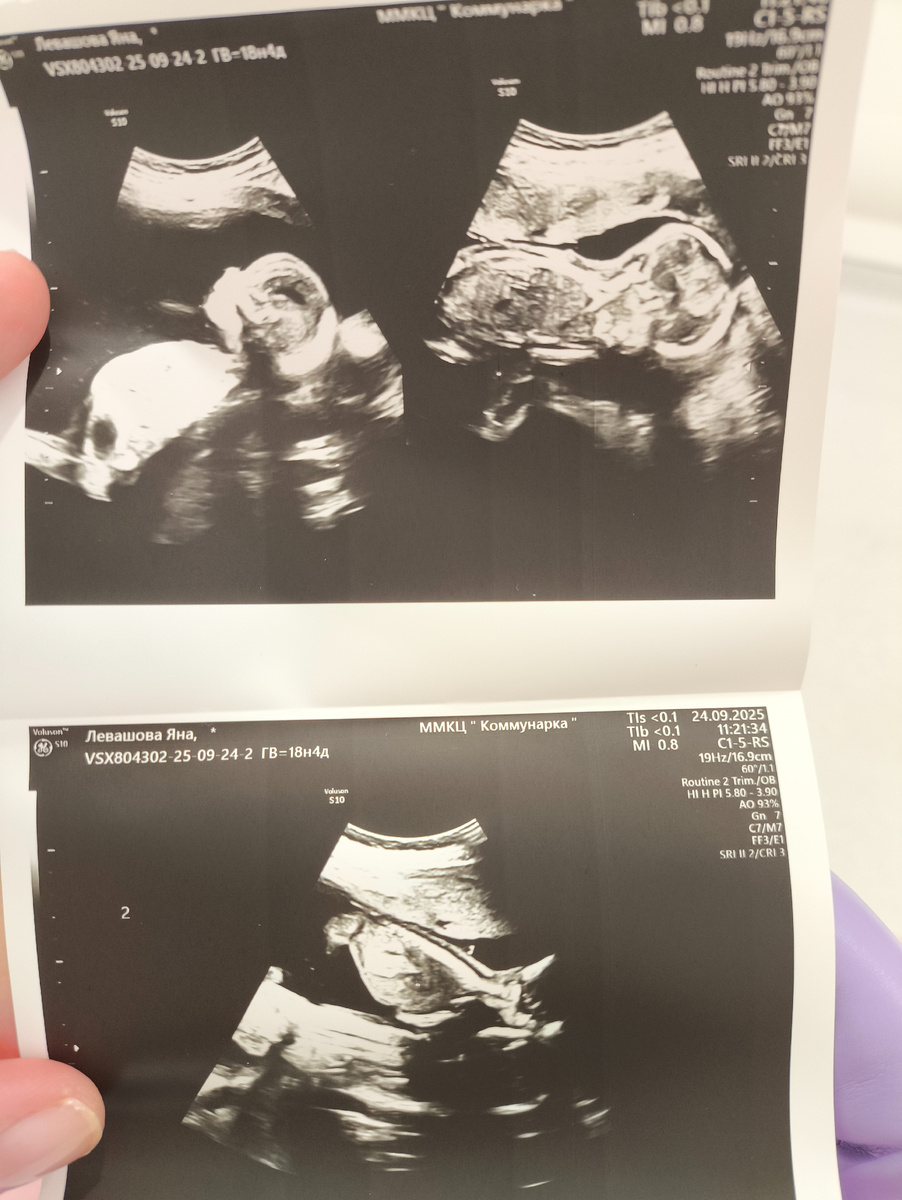

Скрининг в 12 недель. Двойня, многоплодная беременность, наступившая естественным путём, первая в 34 года, я и отец детей совершенно здоровы и без вредных привычек, у плодов одна плацента на двоих. Называется монохориальная диамниотическая двойня. Это близнецы, всегда один пол и одинаковая внешность.

Затем на 12 недель во время скрининга обнаружили мегацестис у одного из двух плодов, при этом все остальные показатели полностью в норме. Направили на повторное УЗИ через пару дней уже к генетикам, там снова увидели мегацестис.

Также меня спросили, что я думаю по поводу пола, ответила - мальчики, наверное, и...мне подтвердили! :) Но тогда ещё не точно, а в формате предположения.

На УЗИ у плода с бывшим мегацестисом произошло опорожнение мочевого пузыря самостоятельно! Специалист это увидела в динамике. Всё в норме! Носы, руки, ноги и головы у обоих, работающие и правильно развивающиеся почки у того, где был мегацестис. Ура! Инвазия отменена.

Новая история. Опять патология, но иная

Теперь у плода, с которым всё было хорошо ещё 3 недели назад, есть риски. Ставят развитие Фето-фетального трансфузионного синдрома(ФФТС), задержки развития одного из плодов, его вес немного меньше, мочевой пузырь очень маленький, нашли со второй попытки, есть явный недостаток амниотической жидкости.

У меня получилось так, что на первом УЗИ показатели 7.2 и 2.1 чуть-чуть не дотягивают до критического состояния, требующего срочного лечения. По таблицам критичны показатели размеров кармана больше 8 и меньше 2 см. Это порадовало и дало надежду на самостоятельное исправление ситуации, по словам врачей.

Скоро всё свершится, судьба решит всё по-своему, но надежда сохранить обоих была, по словам докторов. Меня направили в Коммунарку, доктор Астхик Норайровна Григорян - зав.отделением Антенатальной охраны плода. Впервые после 12-недельного скрининга увидела на экране своих мальчиков. Один из них был таким худым и обтянутым, почти без воды и движения, что я не смогла сдержать слез, экран выключили. Доктор меня успокоила, как-будто знала давно, хотя видела впервые.